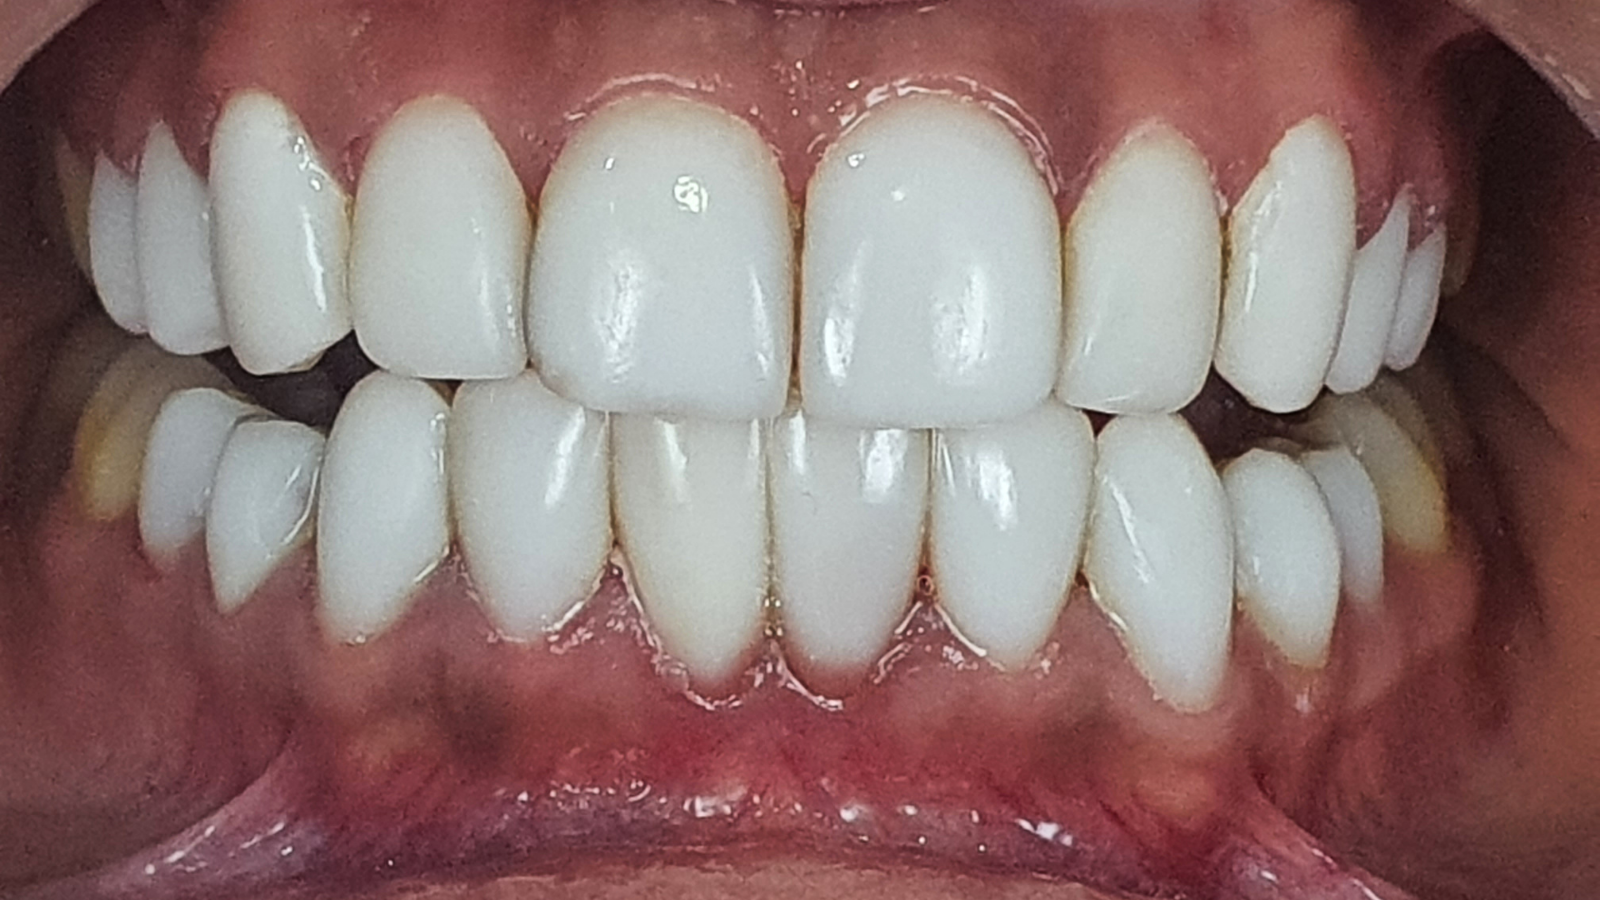

Remplacement de facettes : plus d’harmonie, de translucidité et respect gingival

Une jeune patiente se présente avec des facettes peu esthétiques, opaques et à la forme carrée.

Elles ont été remplacées par de nouvelles facettes aux formes plus harmonieuses, avec davantage de translucidité et surtout une meilleure intégration au niveau de la gencive.

Les images “Après” mettent en évidence un sourire plus naturel, plus lumineux, et une transition plus douce entre la dent et la gencive.

Images :